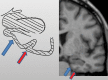

Neurodegenerative diseases are a devastating group of disorders that can be difficult to accurately diagnose. Although these disorders are difficult to manage owing to relatively limited treatment options, an early and correct diagnosis can help with managing symptoms and coping with the later stages of these disease processes. Both anatomic structural imaging and physiologic molecular imaging have evolved to a state in which these neurodegenerative processes can be identified relatively early with high accuracy. To determine the underlying disease, the radiologist should understand the different distributions and pathophysiologic processes involved. High-spatial-resolution MRI allows detection of subtle morphologic changes, as well as potential complications and alternate diagnoses, while molecular imaging allows visualization of altered function or abnormal increased or decreased concentration of disease-specific markers. These methodologies are complementary. Appropriate workup and interpretation of diagnostic studies require an integrated, multimodality, multidisciplinary approach. This article reviews the protocols and findings at MRI and nuclear medicine imaging, including with the use of flurodeoxyglucose, amyloid tracers, and dopaminergic transporter imaging (ioflupane). The pathophysiology of some of the major neurodegenerative processes and their clinical presentations are also reviewed; this information is critical to understand how these imaging modalities work, and it aids in the integration of clinical data to help synthesize a final diagnosis. Radiologists and nuclear medicine physicians aiming to include the evaluation of neurodegenerative diseases in their practice should be aware of and familiar with the multiple imaging modalities available and how using these modalities is essential in the multidisciplinary management of patients with neurodegenerative diseases.©RSNA, 2020.